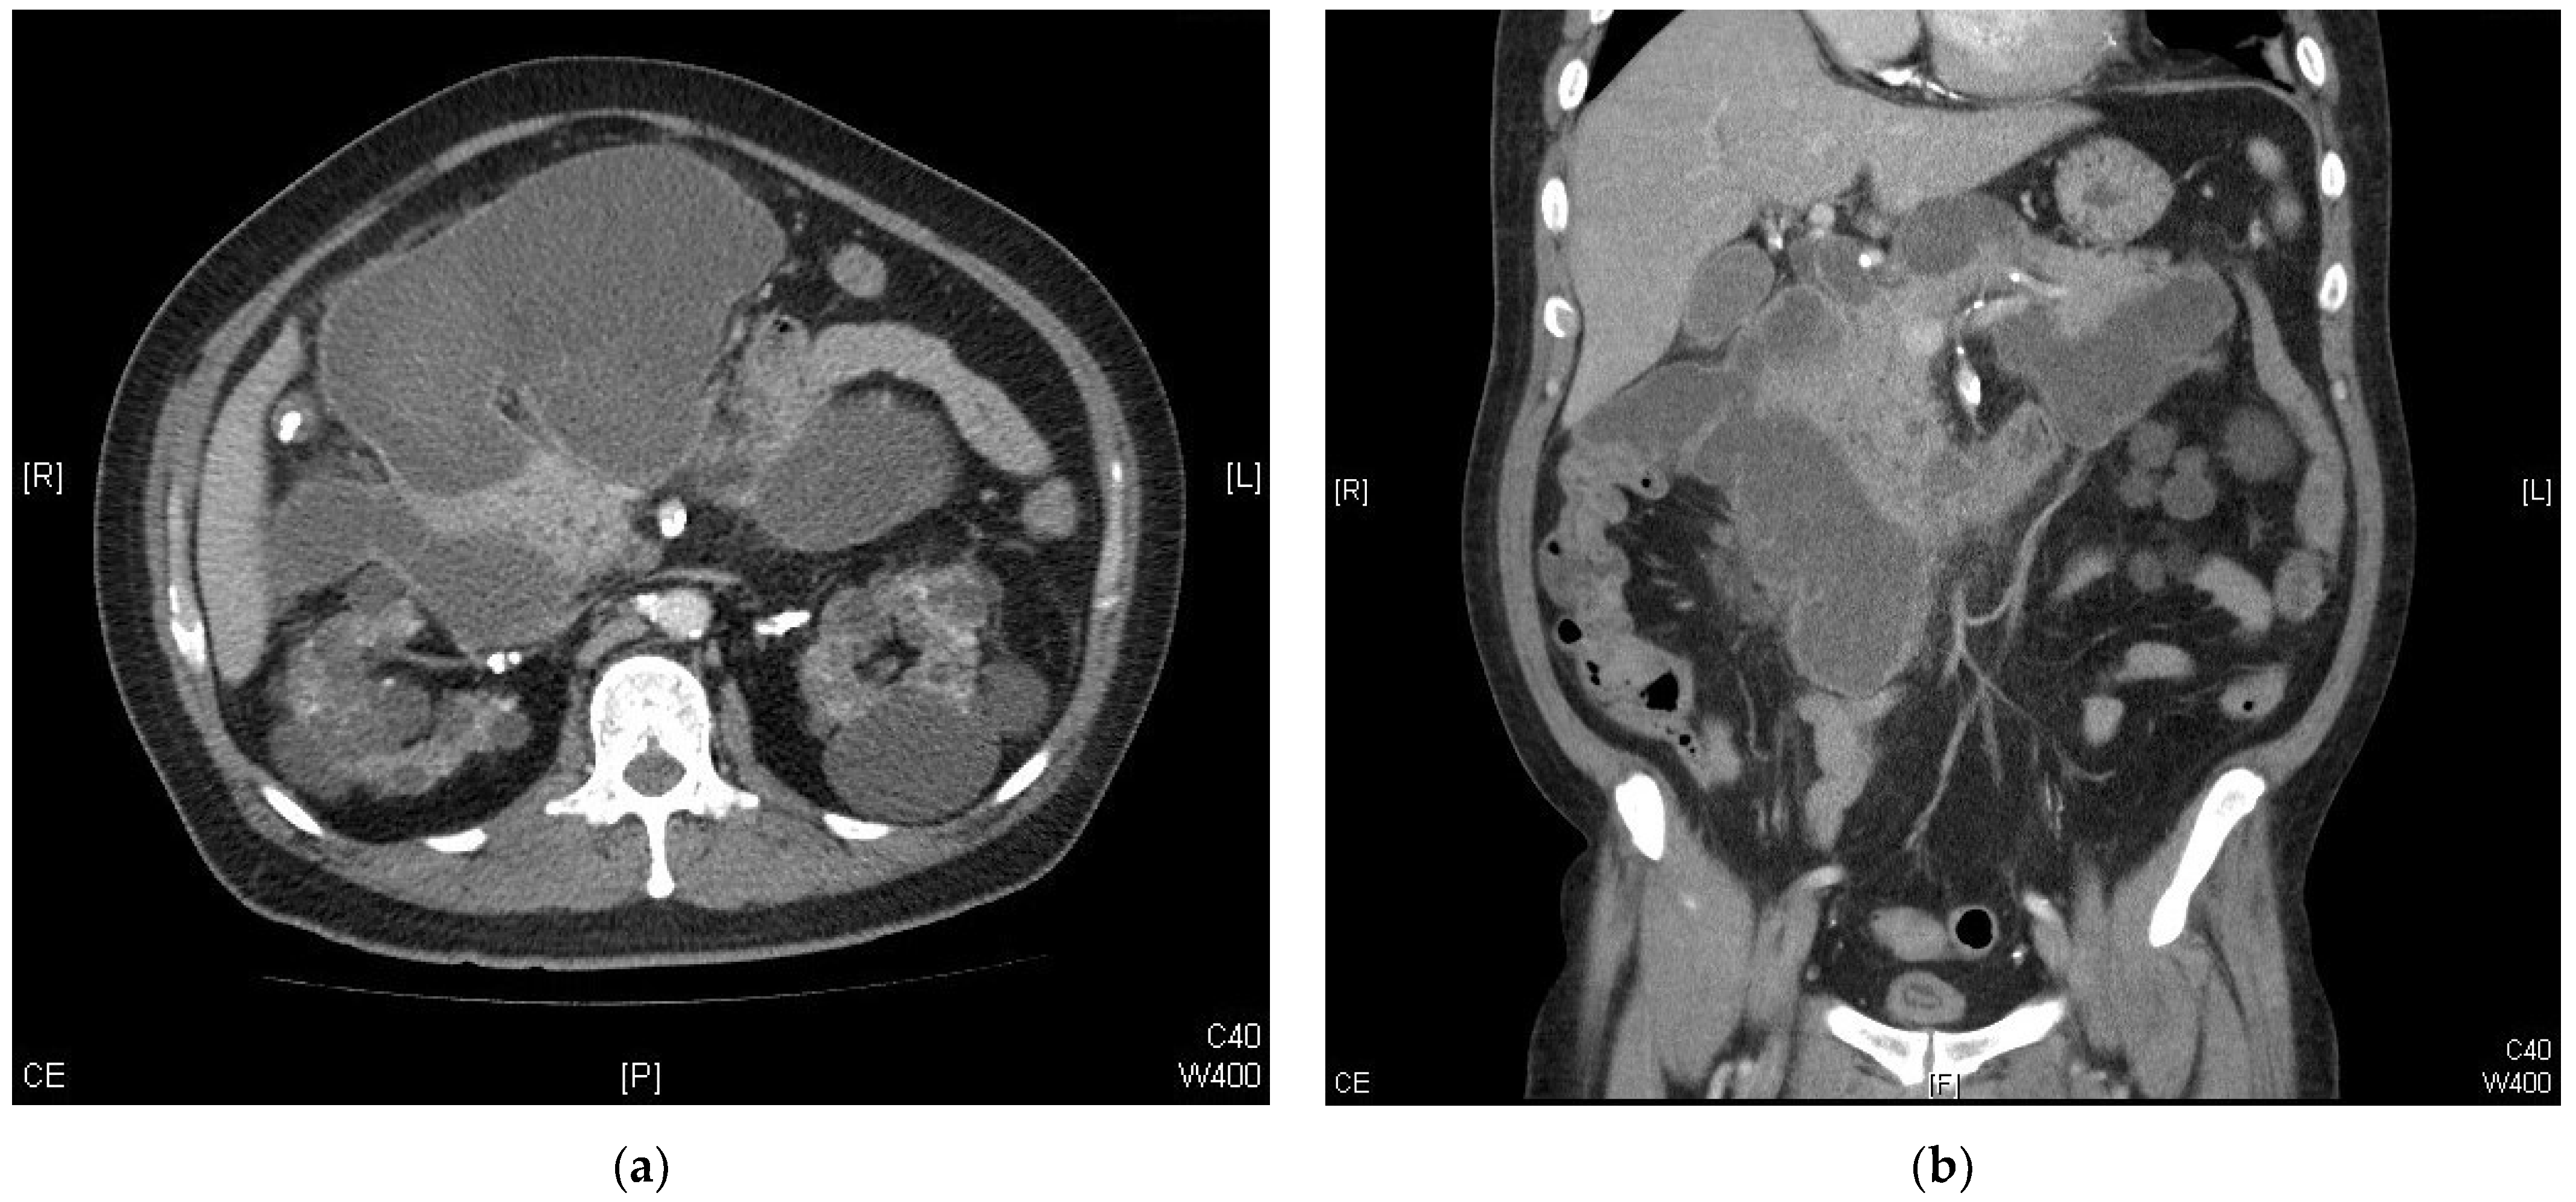

Giant Pancreatic Pseudocyst after Coronary Artery Bypass Graft in a Hemodialysis Patient: A Case Report

2. Case Report